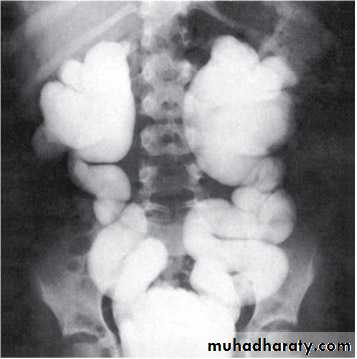

Grading of VUR

The degree of reflux is graded I–V.Grading is based on the appearance of contrast agent in the collecting system during voiding cystourethrography (VCUG(.

COMPLICATIONS

Hydroureteronephrosis(1) Increased work load

(2) High hydrostatic pressure

(3) Weak ureteral musculature